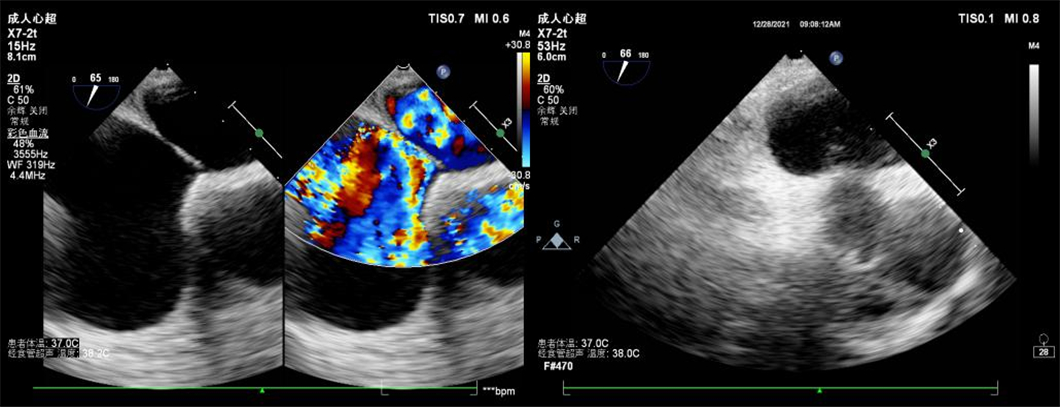

患者1

据了解,部分患者行经胸超声心动图检查时,因自身条件、检查方式等客观原因,导致较小的心脏疾病容易漏诊。然而,经食管超声心动图检查作为经胸超声心动图的补充检查,可以更加直观、清晰地观察心脏内部结构,在先天性心脏病、瓣膜性心脏病、心脏肿瘤、血栓等疾病诊断中具有重要意义。尤其是在持续性头痛、不明原因脑卒中、动脉栓塞等患者中,可能会存在卵圆孔未闭这一心脏疾病。经食管超声心动图联合由右心声学造影检查可清楚显示卵圆孔的结构、大小、形态,分别在患者静息状态及Valsava动作下,通过观察房间隔卵圆孔处血流信号、造影剂微气泡的分流情况,准确诊断卵圆孔未闭,从而指导临床医生及时治疗,有效预防患者潜在脑血管意外事件的发生。